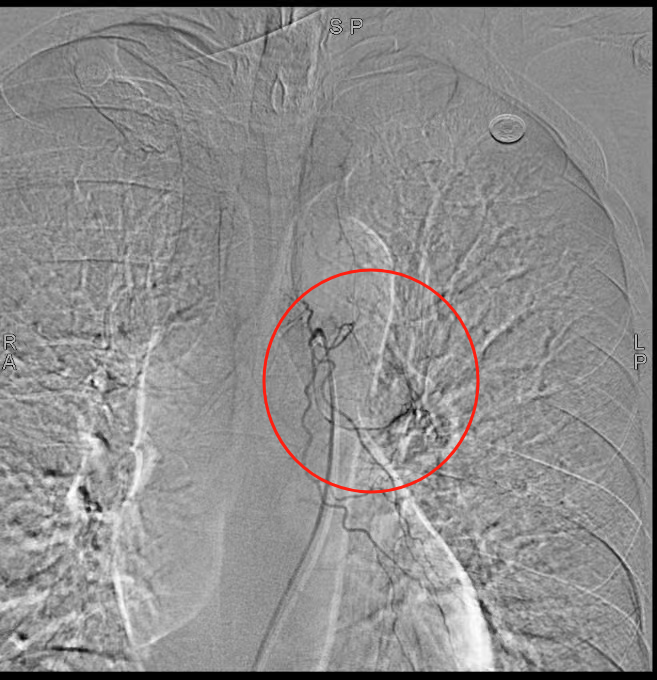

58岁的汪先生(化名)因大咯血入院,虽生命体征平稳,但出血症状持续未缓解。经支气管镜检查发现,其左侧支气管内存在浸润性新生物,表面血管扭曲、血供丰富,随时可能再次出现大咯血,病情十分凶险。

1.血管介入止血:通过支气管动脉栓塞术紧急控制出血风险;

“支气管淀粉样变发病率极低,极易误诊漏诊!”我院呼吸与危重症医学科副主任(主持工作)王开金副主任医师介绍,该病由淀粉样物质异常沉积于气道引发,临床表现缺乏特异性,确诊必须依赖病理活检。“此例患者出血风险极高,活检操作犹如‘刀尖起舞’。”王开金表示,团队通过血管介入止血、支气管镜精准定位和快速病理检测,实现了“诊断-治疗”一体化,为患者抢得生机。